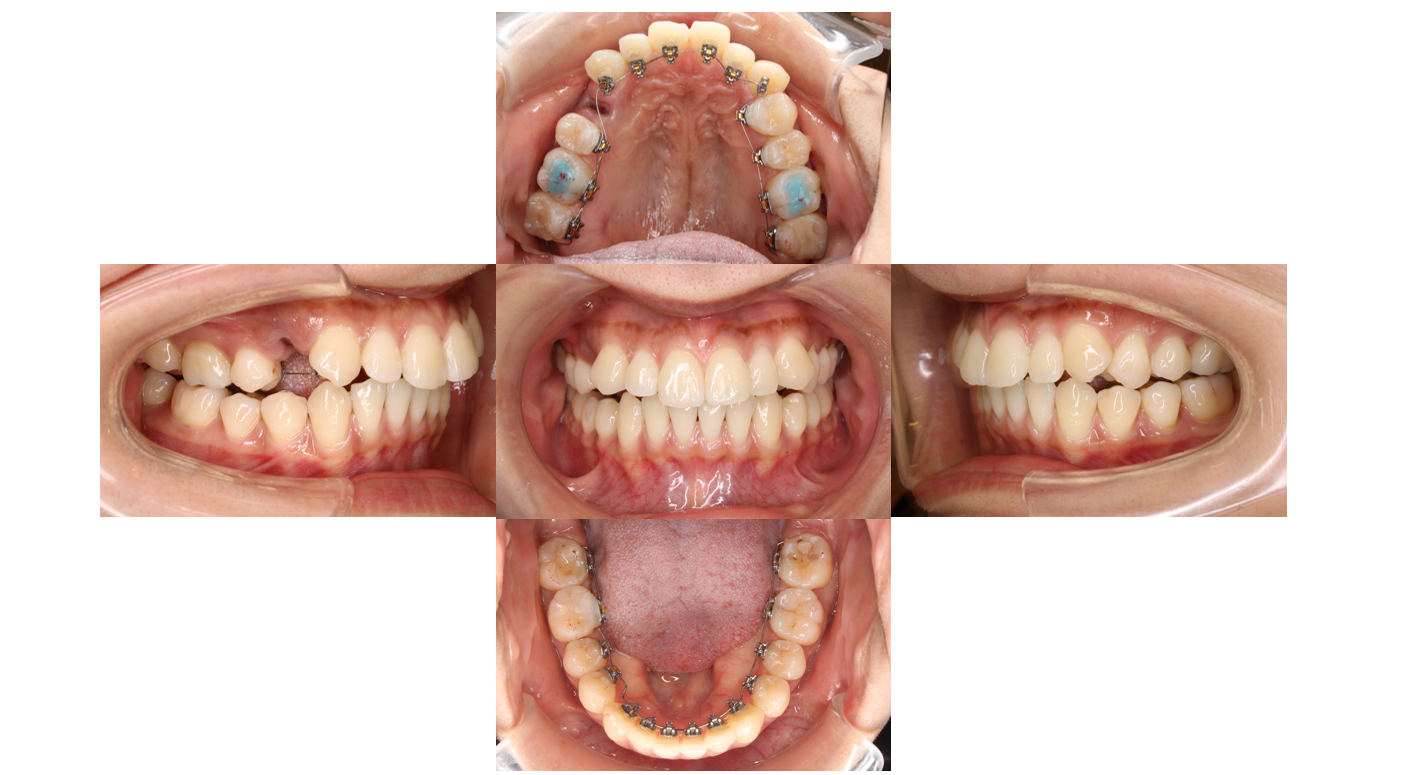

6か月経過

歯並びのがたつきを改善するためにワイヤーのサイズをあげていきます